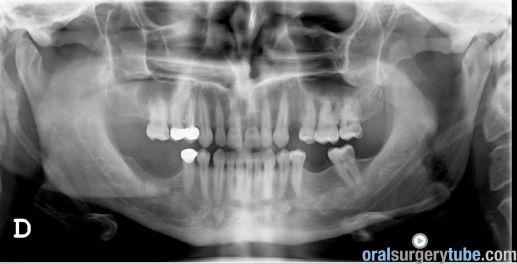

Con este comentario haremos una pausa en el caso hasta que llegue la colocación de los implantes. Por el momento, está todo solucionado. No hay sintomatología alguna, y lo más importante, en TAC realizado el martes 31.07.2018, podemos ver que el seno ha drenado por completo y está aireado. Hasta nuevo aviso, suspendemos todo tipo de medicación. Subimos imágenes del último TAC donde podemos apreciar que hemos perdido algo de xenoinjerto, pero la zona de menor altura aún tiene 10 mm. Podemos ver en una de las imágenes la zona de la ventana por donde el seno drenaba. Esperaremos el tiempo reglamentario para poder reevaluar si el xenoinjerto sigue siendo viable. Ha sido un gran placer contar con este equipo y poder aportar un grano de arena a solucionar complicaciones quirúrgicas.

Respondo a Hernán Rescala: Antes que nada, darte las gracias por tu comentario. Este paciente llevaba dos coronas ferulizadas 1-4; 1-5 cuando le vimos en 2014. En aquel momento, no se hizo ningún tratamiento, y fue una pena. La pieza 16, por la que ha venido toda esta historia era recuperable. Quizás no supimos convencerle de intervenir de inmediato, de lo cual me culpo. Subo panorámica de 2014. Volvió en 2018 con las coronas caídas y el pilar 1-4 totalmente destruido. La pieza 1-5 era vital y colocamos un provisional, el cual descementó varias veces. La 1-4 decidimos mantenerla para hacer un implante cuando colocáramos los demás. El dia de la cirugía del seno, vino con el provisional roto, pero al no tener mucha sensibilidad en la pieza, intervinimos y lo dejamos tal cual. Después de tu observación volvimos a valorar esta pieza el viernes 13 con un test pulpar y Rx, que subo. La pieza sigue vital, con pruebas frio, calor y eléctrica(12 en escala 1-100). Subo TAC previo

Continúo con el seguimiento que vamos dando a este paciente: Visitado el miércoles 11.07.2018. Hay ausencia total de sintmatología. Retiramos el drenaje, hacemos Prueba de Valsalva positiva, pero sale aire y un poco de sangre. Dejamos cicatrizar por segunda intención. Pedimos continuar la medicación antibiótica y solicitamos un TAC. El seno maxilar está ocupado como vemos en la imagen, pero el biomaterial está contenido en la zona injertada: no existe ningún gránulo de xenoinjerto dentro del seno. La apófisis mastoidea está aireada.